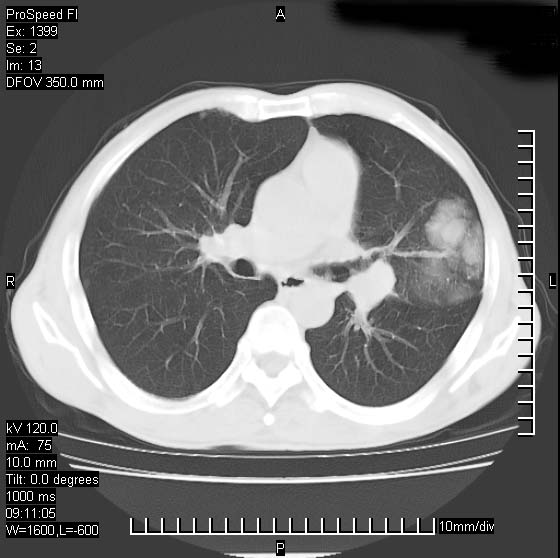

以下是引用rgsyyf在2007-1-19 11:05:00的发言:[br]左肺上叶见形态不规则巨大软组织肿块影,边缘呈分叶征,纵隔内隆突下见肿大淋巴结,右肺内另见一不规则结节影 .考虑:左肺周围性肺癌伴纵隔即右肺内转移.